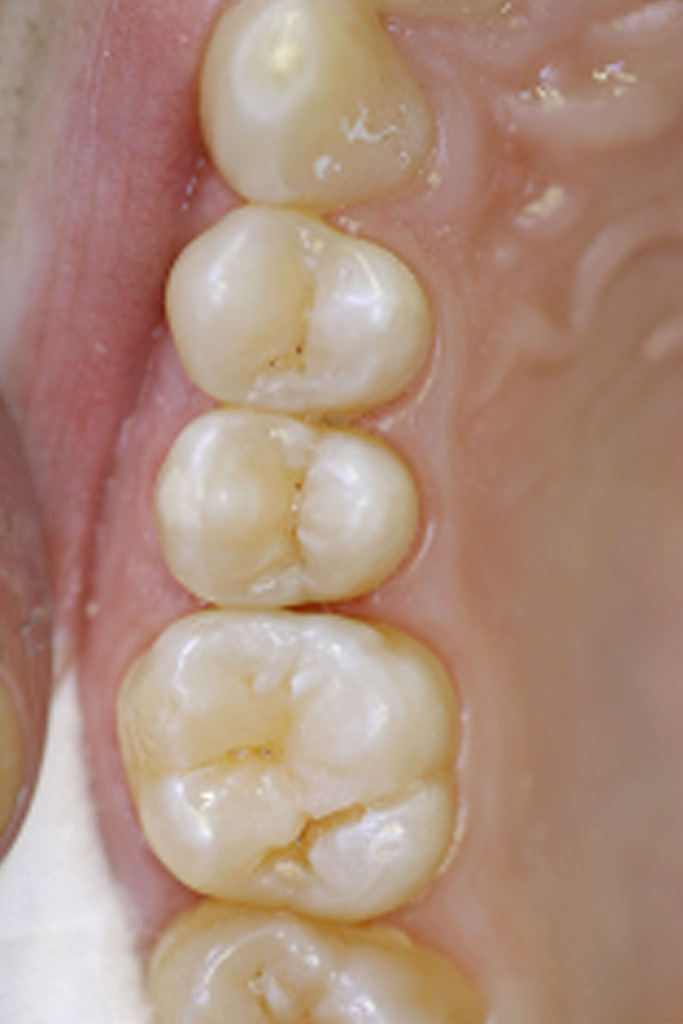

Behandlungsbeispiel:

Allerdings wäre es verfrüht, davon auszugehen, dass man anstatt dem Bohrer überall den Laser einsetzen kann. Nicht eingesetzt werden kann der Laser z.B. zum Entfernen alter Amalgamfüllungen, da ansonsten giftige Quecksilberdämpfe entstehen könnten. Solcherart vorhandene alte Füllungen müssen vor dem Lasereinsatz mit dem konventionellen Bohrer entfernt werden. Der Laser wird in der Regel auch nicht eingesetzt um große Füllungen vorzubereiten. Er ist zwar angenehmer aber gegenüber dem konventionellen Bohrer deutlich langsamer. Daher eignet sich das Laserbohren vor allem bei kleineren kariösen Defekten. Hier stehen an erster Stelle Behandlungen im Frontzahnbereich und im gut zugänglichen Seitenzahnbereich im Vordergrund.

Ein großer Vorteil liegt beim Bohren mit dem Laser darin, dass durch das punktförmige Abtragen der Zahnhartsubstanz das präparierte Loch (= Kavität) in seiner Ausdehnung äußerst klein gehalten werden kann. Dadurch kann im Gegensatz zum konventionellen Bohren mehr gesunde Zahnsubstanz erhalten werden. Solchermaßen schonend vorbereitete Kavitäten eignen sich besonders zur Versorgung mit weißem Füllmaterialien, also z.B. Composite. Dies ist ein weiterer Beitrag des Lasers, kosmetisch anspruchsvolle Füllungen zu ermöglichen.

Einziger Nachteil bleibt die längere Behandlungszeit wegen der langsameren Abtragsgeschwindigkeit des Lasers gegenüber dem Bohren mit der Turbine.